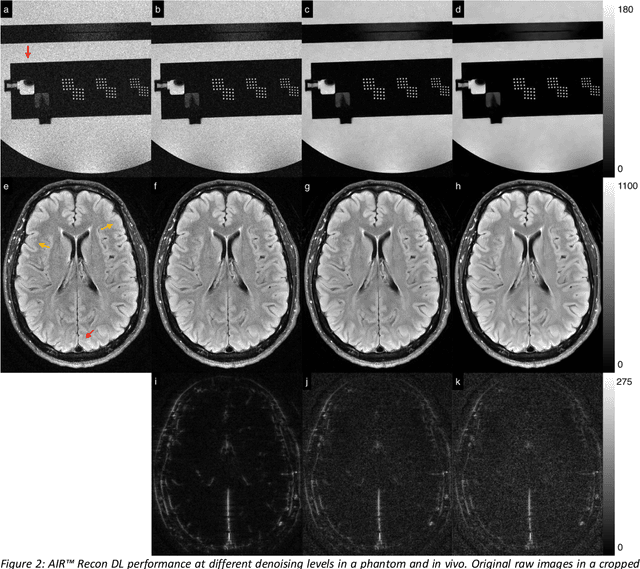

A novel deep learning-based magnetic resonance imaging reconstruction pipeline was designed to address fundamental image quality limitations of conventional reconstruction to provide high-resolution, low-noise MR images. This pipeline's unique aims were to convert truncation artifact into improved image sharpness while jointly denoising images to improve image quality. This new approach, now commercially available at AIR Recon DL (GE Healthcare, Waukesha, WI), includes a deep convolutional neural network (CNN) to aid in the reconstruction of raw data, ultimately producing clean, sharp images. Here we describe key features of this pipeline and its CNN, characterize its performance in digital reference objects, phantoms, and in-vivo, and present sample images and protocol optimization strategies that leverage image quality improvement for reduced scan time. This new deep learning-based reconstruction pipeline represents a powerful new tool to increase the diagnostic and operational performance of an MRI scanner.